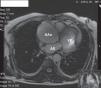

Na admissão no nosso hospital, o doente encontrava-se assintomático, sob terapêutica com nitratos e beta-bloqueante e hemodinamicamente estável. Realizou ressonância magnética cardíaca que evidenciou a dilatação aneurismática da aorta limitada à raiz da aorta e aorta ascendente (diâmetro transverso máximo: 65mm), excluindo a hipótese de dissecção ou rutura (Figuras 3 e 4). O cateterismo cardíaco pré-operatório excluiu doença coronária e a aortografia, efetuado no mesmo ato, documentou ectasia anulo-aórtica (diâmetro transverso máximo de 75mm, ao nível da aorta ascendente) (Figura 5). Assim, o doente foi submetido a cirurgia, tendo sido efetuada a operação de Bentall com implantação de próteses valvular aórtica Carpentier n.° 25 e tubular Vascutek n.° 28. O pós-operatório decorreu sem intercorrências e o doente teve alta 5 dias depois. A análise anátomo-patológica da parede arterial ressecada mostrou numerosas placas de aterosclerose, com ulceração focal.